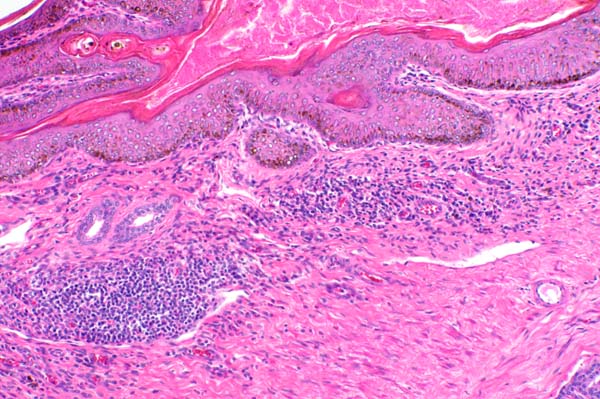

The epithelium is mildly hyperplastic and inflammatory cells infiltrate the superficial dermis.